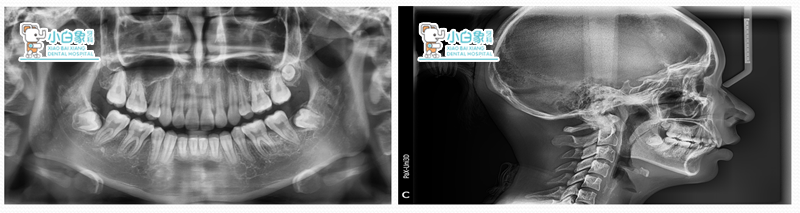

患者:***    女     14岁

主诉:牙不齐,求治。

现病史:患者换牙后发现牙列不齐,影响美观,来诊。

初诊时间:2014.07.08

结束时间:2017.05.17

问题清单:

安氏二类一分类错合

上颌前突,下颌后缩

11.21唇倾,32.42舌倾

深覆合三度 深覆盖三度

治疗计划:

全口直丝弓固定矫治术(LF)

拔除15.25.35.45

排齐与整平牙弓

关闭拔牙间隙

解决覆合覆盖及咬合关系保持

总结:

总体来说比较满意。

上颌突度改善较大,面型有改观,咬合关系从二类变为一类,深覆合、深覆盖得到很好的解决。

不足:下前牙角度没有控制好,倾斜度较大。